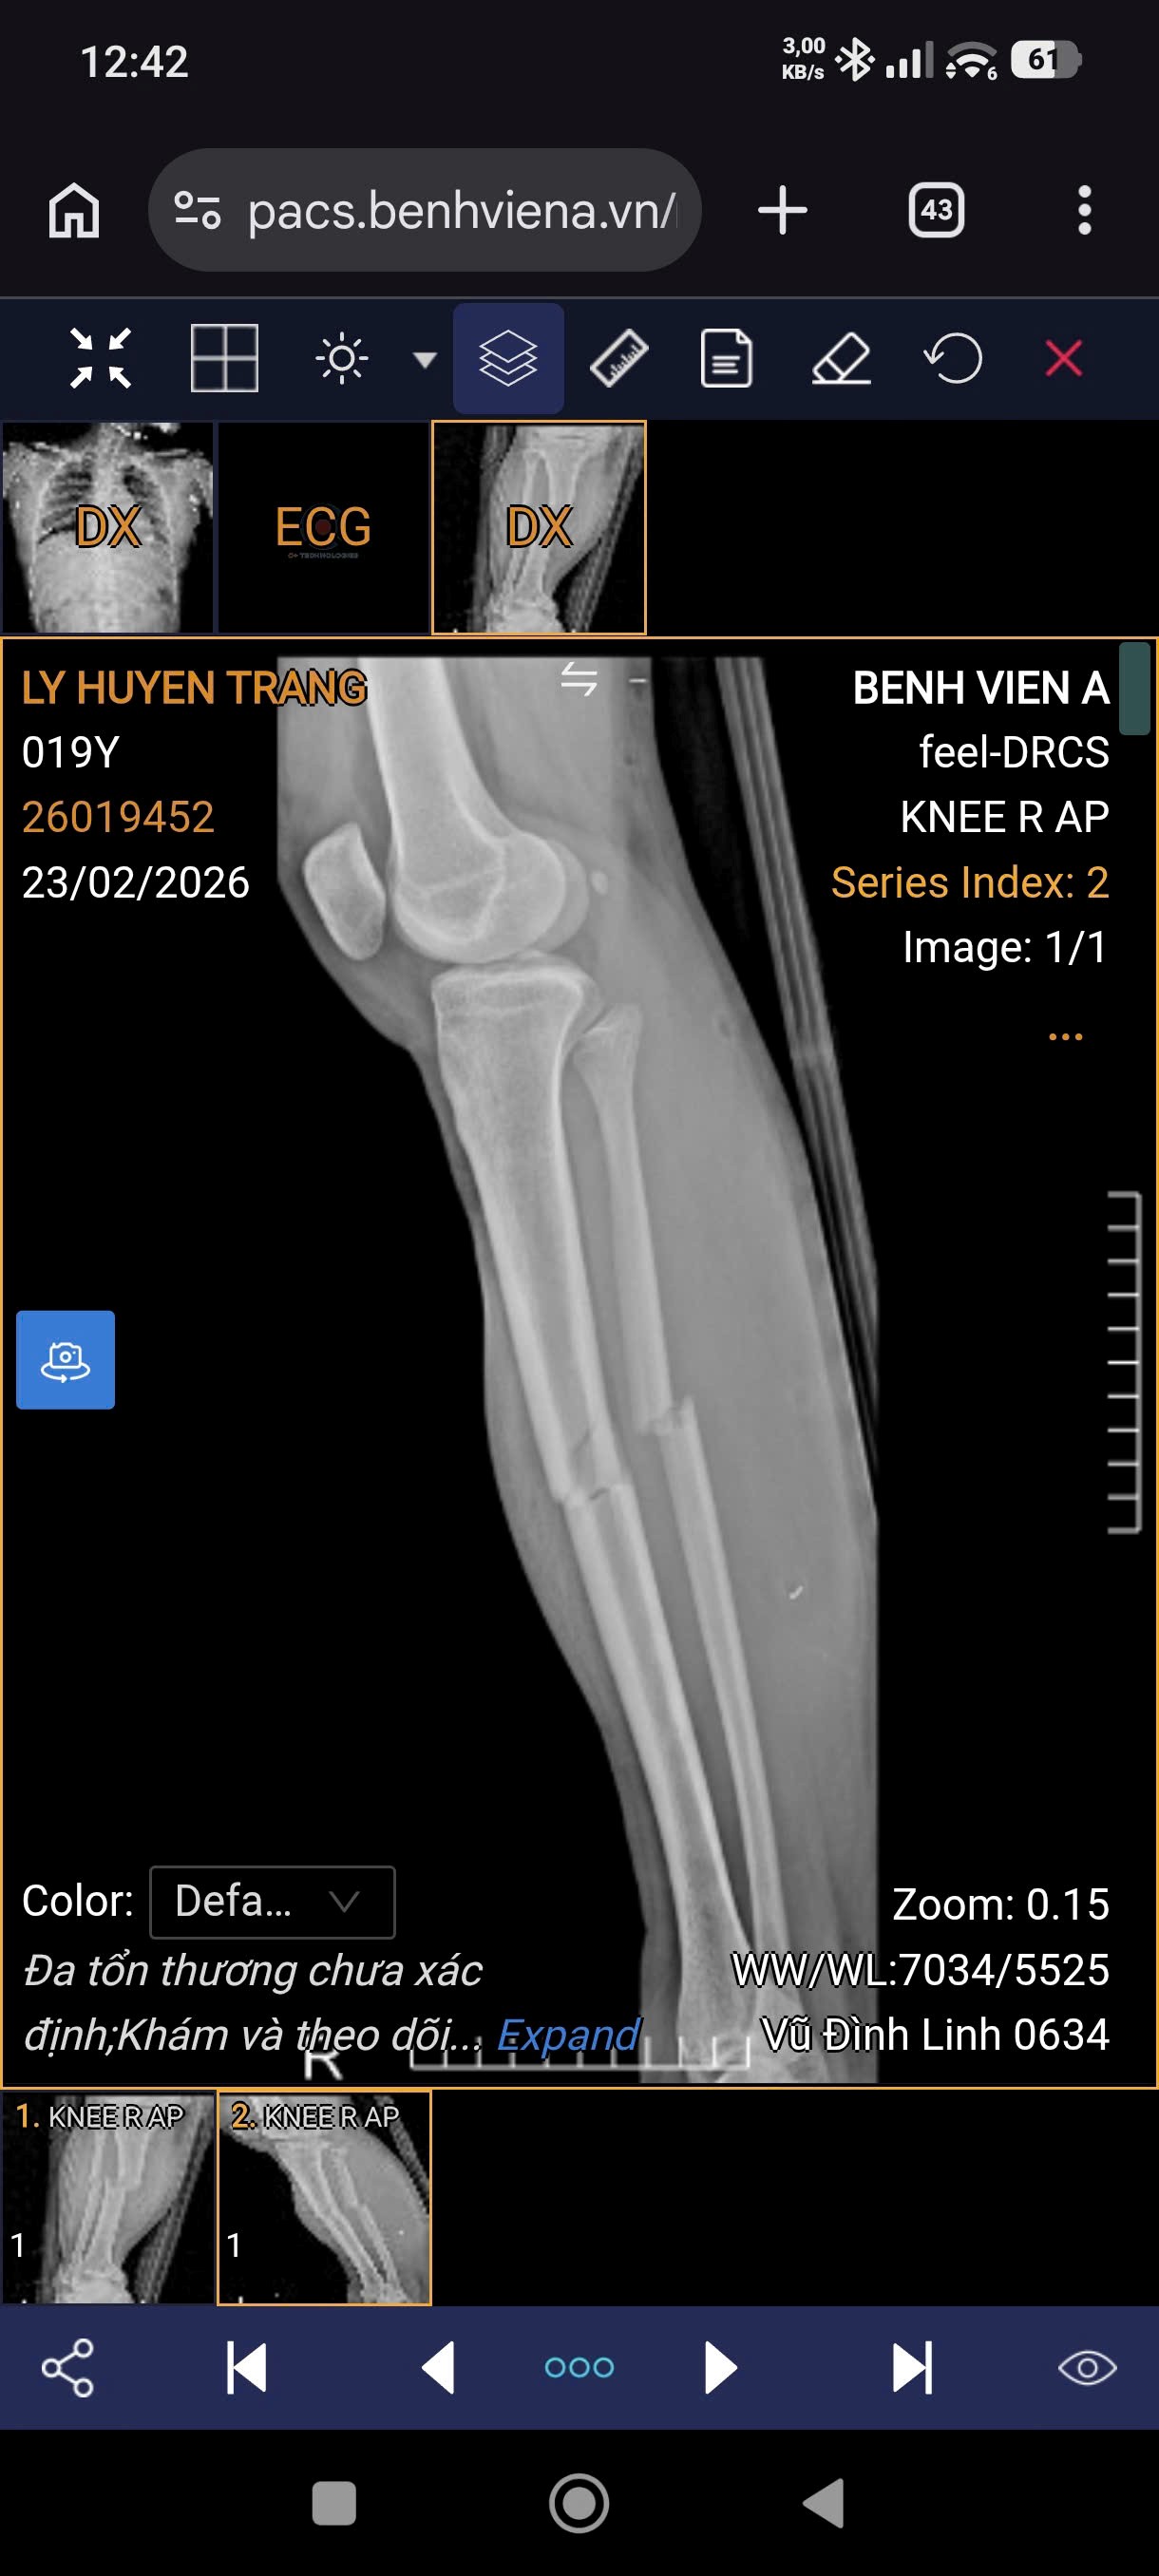

Hình ảnh X-quang bệnh nhân nữ 19 tuổi, gãy 1/3 giữa hai xương cẳng chân phải do tai nạn giao thông.